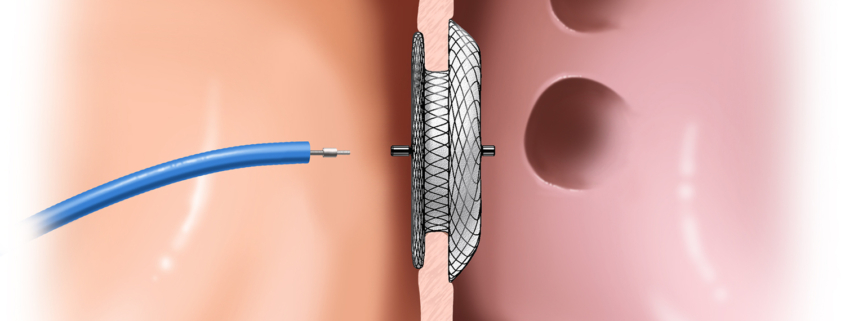

Atrijski septalni defekt (ASD) je prekid kontinuiteta mišićne pregrade (lat. interatrijski septum) koja odjeljuje dvije srčane pretklijetke (atrija).